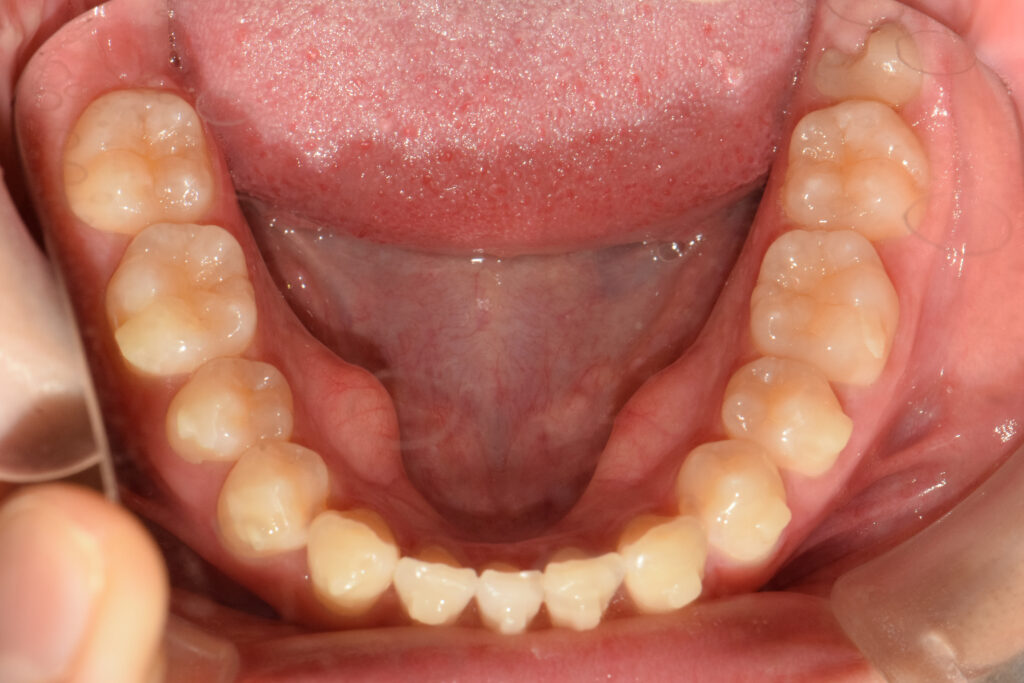

下顎

治療後